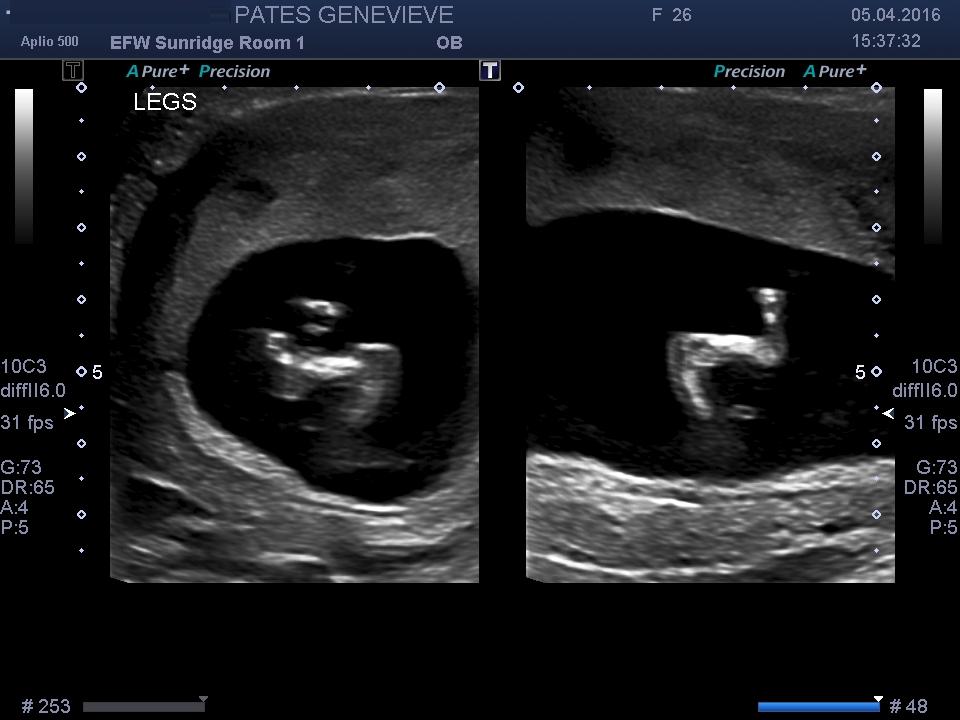

It's a hard one not the clearest nub pic. I would lean a boy I think you can see stacking but it could just be shadows and still a girl. I'm 50/50